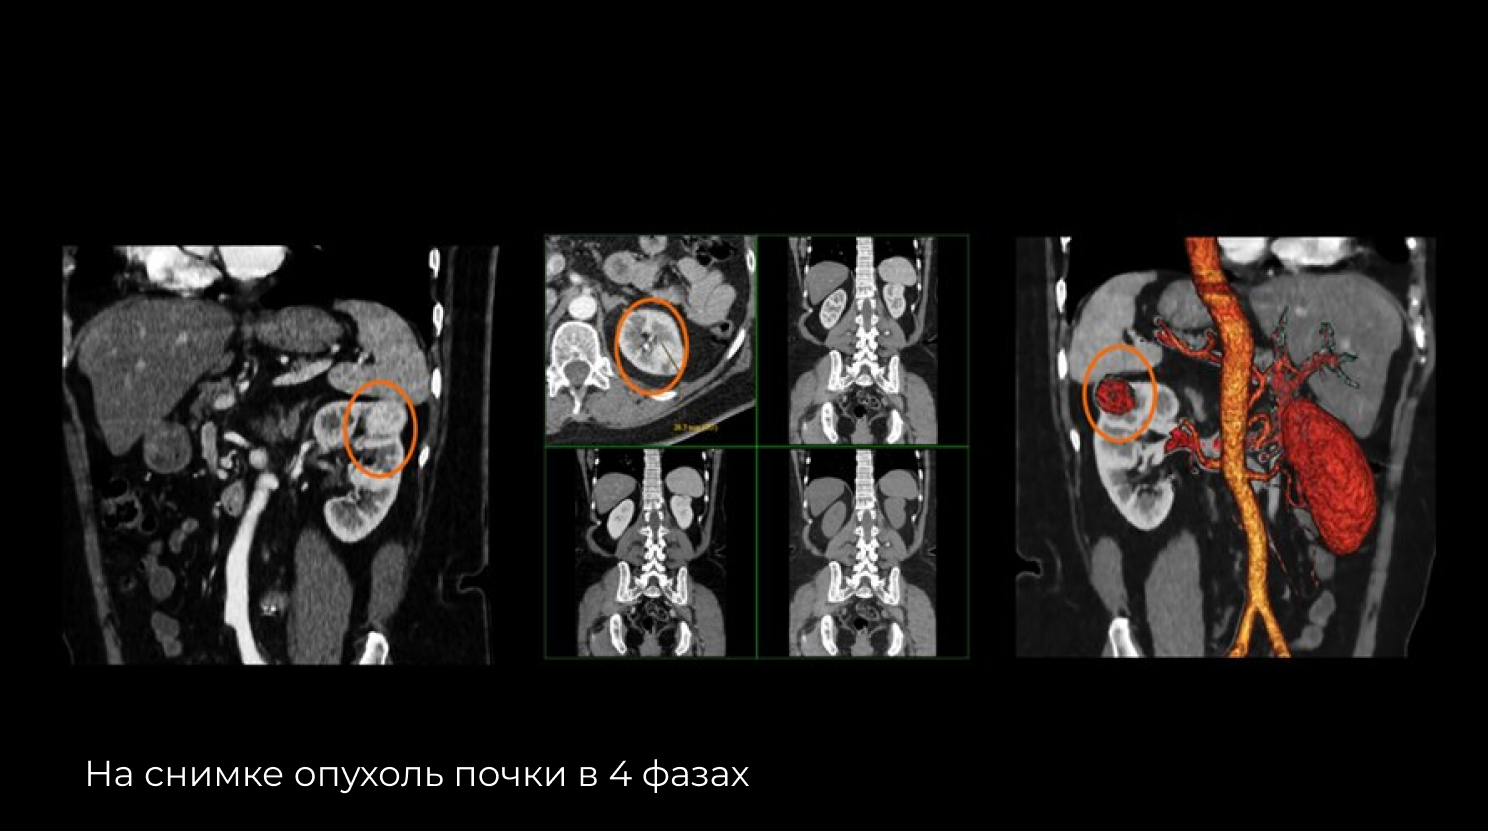

Optima ct520 115 фото